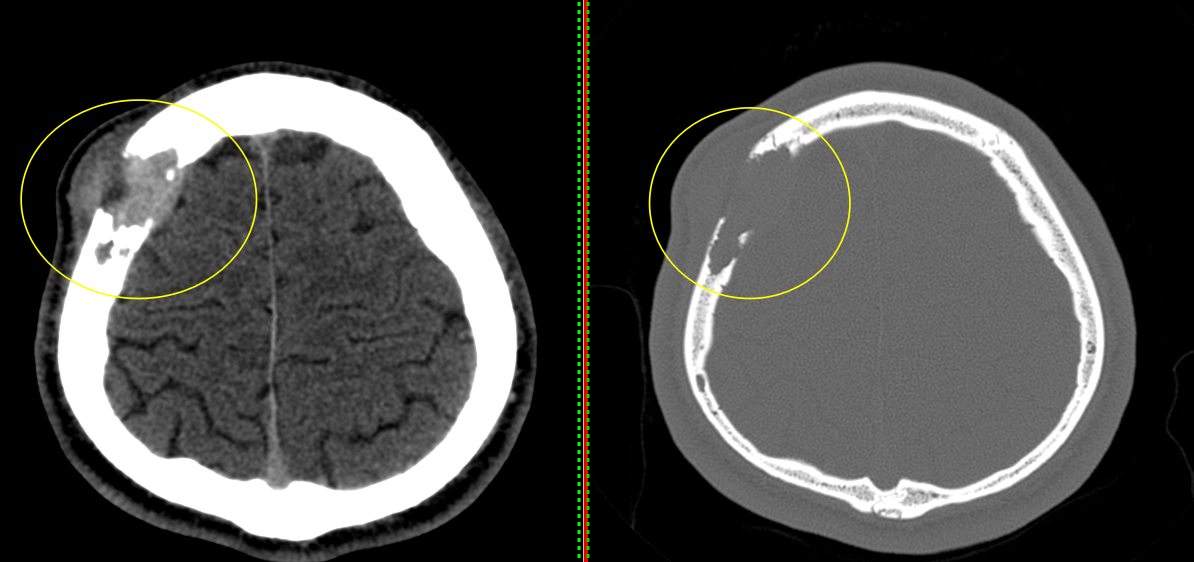

A. Imagistică:

- Radiografie craniană: utilă pentru modificări osoase evidente.

- CT cranian cu reconstrucție 3D: evidențiază detalii osoase.

A. Osteosarcomul cranian

Tumoră osoasă malignă ce produce os imatur.

Rară la nivelul craniului, dar agresivă.

Simptome: masă dură, durere, edem, uneori pareze nervoase.

Apare uneori după radioterapie.

Tratament: chirurgie radicală + chimioterapie.

5. Tumori secundare (metastatice)

Metastazele osoase la nivelul craniului apar mai ales în cancerele de sân, prostată, plămân, rinichi și tiroidă.

Pot afecta calota craniană, baza craniului sau orbita.

Simptome: durere locală, deformare, uneori invazie în cavitatea craniană.

Diagnosticul include CT/RMN, PET-CT.

Tratament: radioterapie, terapie sistemică (chimioterapie, terapie hormonală), excizie chirurgicală în cazuri selectate.

A. Tratamentul chirurgical:

Este principala formă de tratament pentru tumorile benigne și multe dintre cele maligne. Scop: rezecția completă cu margini negative, menținând funcțiile neurologice. Dacă tumora nu invadează meningele, riscurile neurologice sunt reduse; pe de altă parte, atunci când tumora se extinde și la nivelul durei mater sau chiar al creierului, este posibil ca excizia tumorii să fie subtotală sau parțială, pentru a proteja structurile nervoase.

Un timp important al operației îl reprezintă reconstrucția calotei craniene, care se face cu plăci ceramice customizate, mesh din titan sau ciment acrilic modelat pe loc. Uneori, datorită invaziei tegumentului, sunt necesare intervenții complexe de chirurgie plastică pentru refacerea defectului la nivelul scalpului.